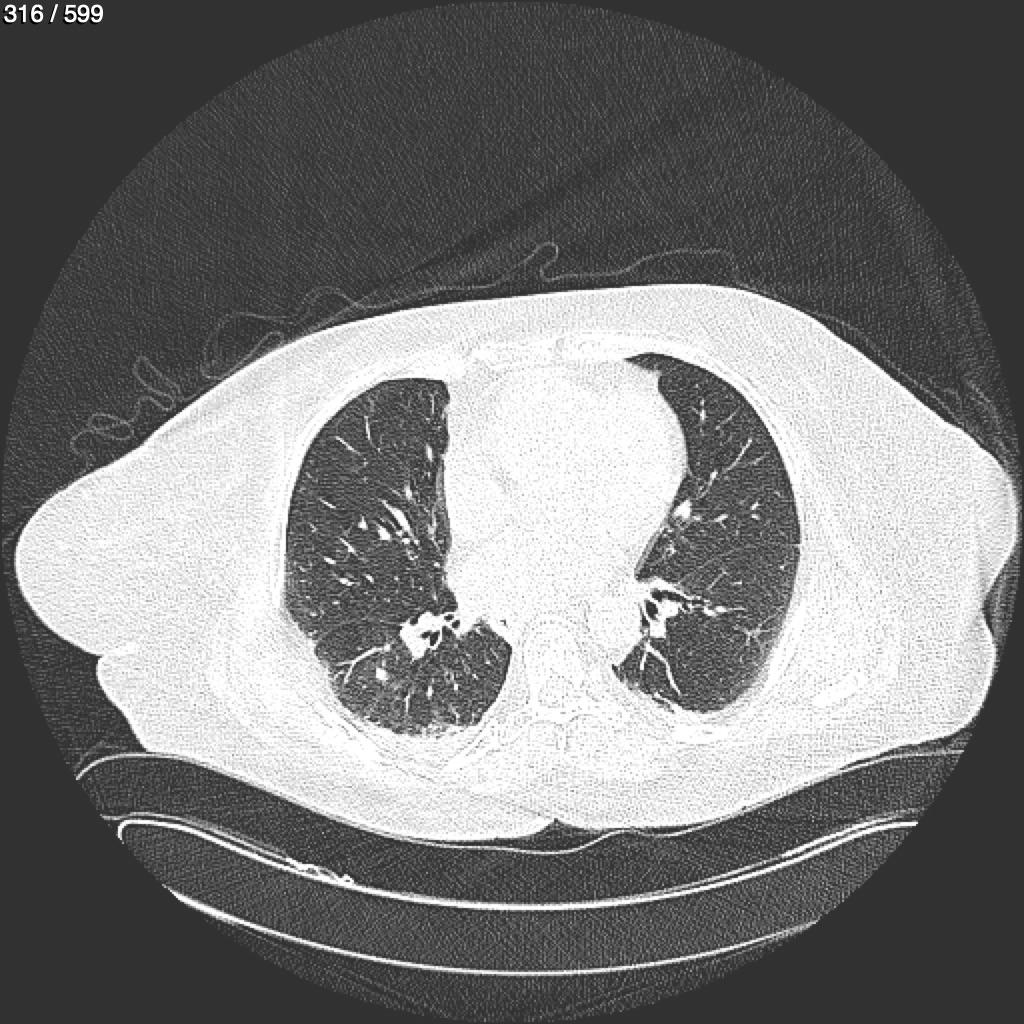

Home G​l​o​r​i​a​ ​G​l​a​d​y​s​ ​B​e​a​s​l​e​y​ ​-​ ​T​ó​r​a​x​ ​T​o​r​a​x​_​S​i​m​p​l​e​ ​(​A​d​u​l​t​o​)